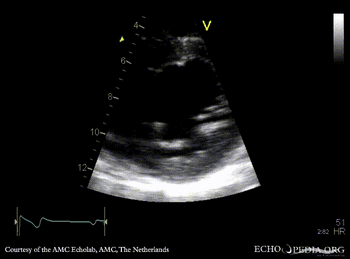

PSAX: double orifice of mitral valve Continuous-wave signal of mitral inflow